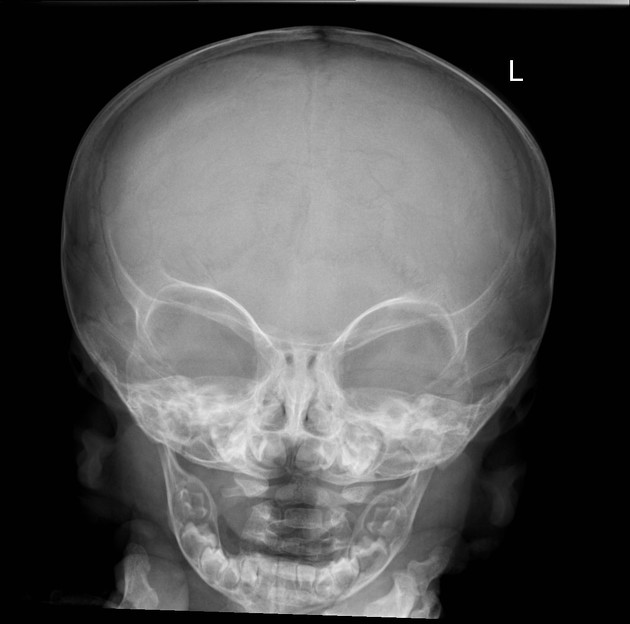

Краниосиностоз

Отсутствие рентгенконтрастной шовной щели между костями черепа, особенно в области сагиттального, коронарного или ламбдовидного швов.

Ассиметрия или деформация черепа (долихоцефалия, скафоцефалия и др.), выявляемая в прямой и боковой проекциях.

Утолщение шовной зоны и изменение рельефа внутренней пластинки свода черепа.

Уплощение отдельных костей черепа с компенсаторной деформацией противоположных участков.